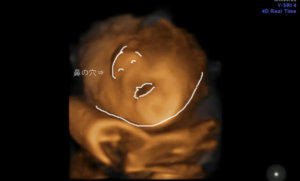

エコーの結果では、すでに出産予定日が過去日付に・・orz